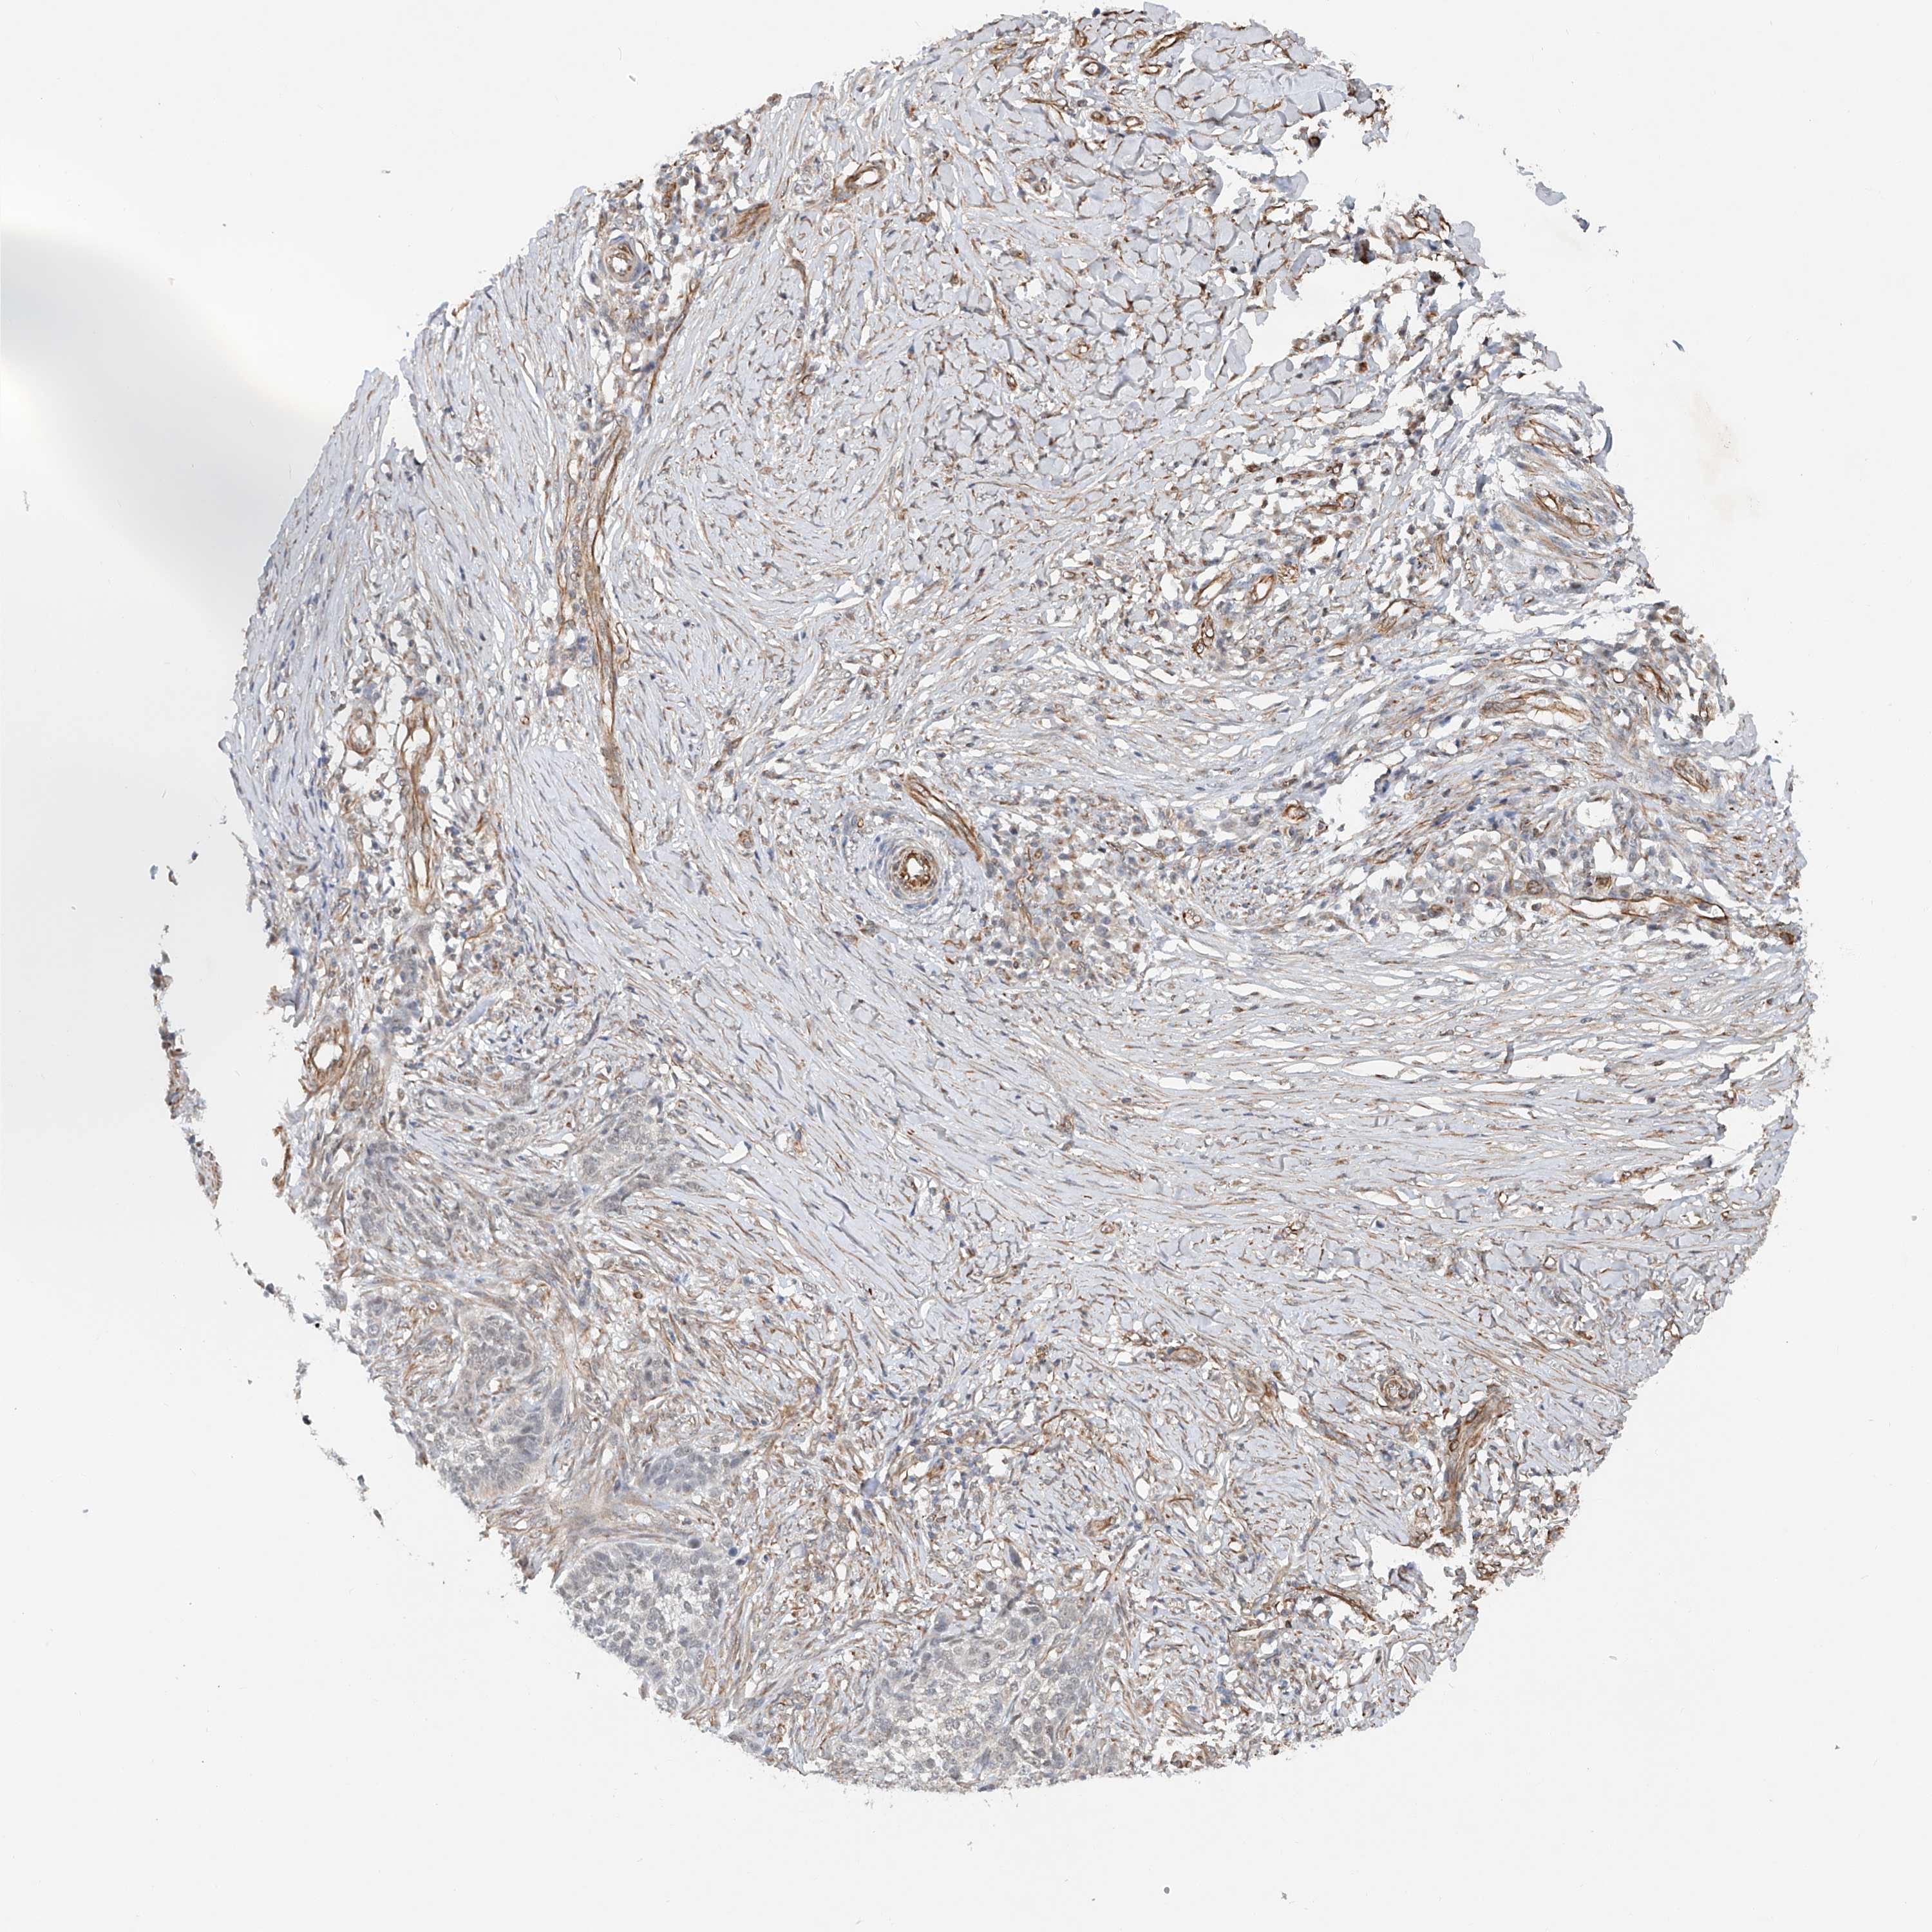

SKIN CANCER - Protein expressioni

A mouse-over function shows sample information and annotation data. Click on an image to view it in a full screen mode. Samples can be filtered based on level of antibody staining by selecting one or several of the following categories: high, medium, low and not detected. The assay and annotation is described here.

Antibody stainingi

Antibody staining in the annotated cell types in the current human tissue is reported as not detected, low, medium, or high, based on conventional immunohistochemistry profiling in selected tissues. This score is based on the combination of the staining intensity and fraction of stained cells.

Each image is clickable and will lead to virtual microscopy that enables deeper exploration of all samples and also displays staining intensity scores, fraction scores and subcellular localization as well as patient and tissue information for each sample.

Antibody HPA029282

Squamous cell carcinoma, NOS